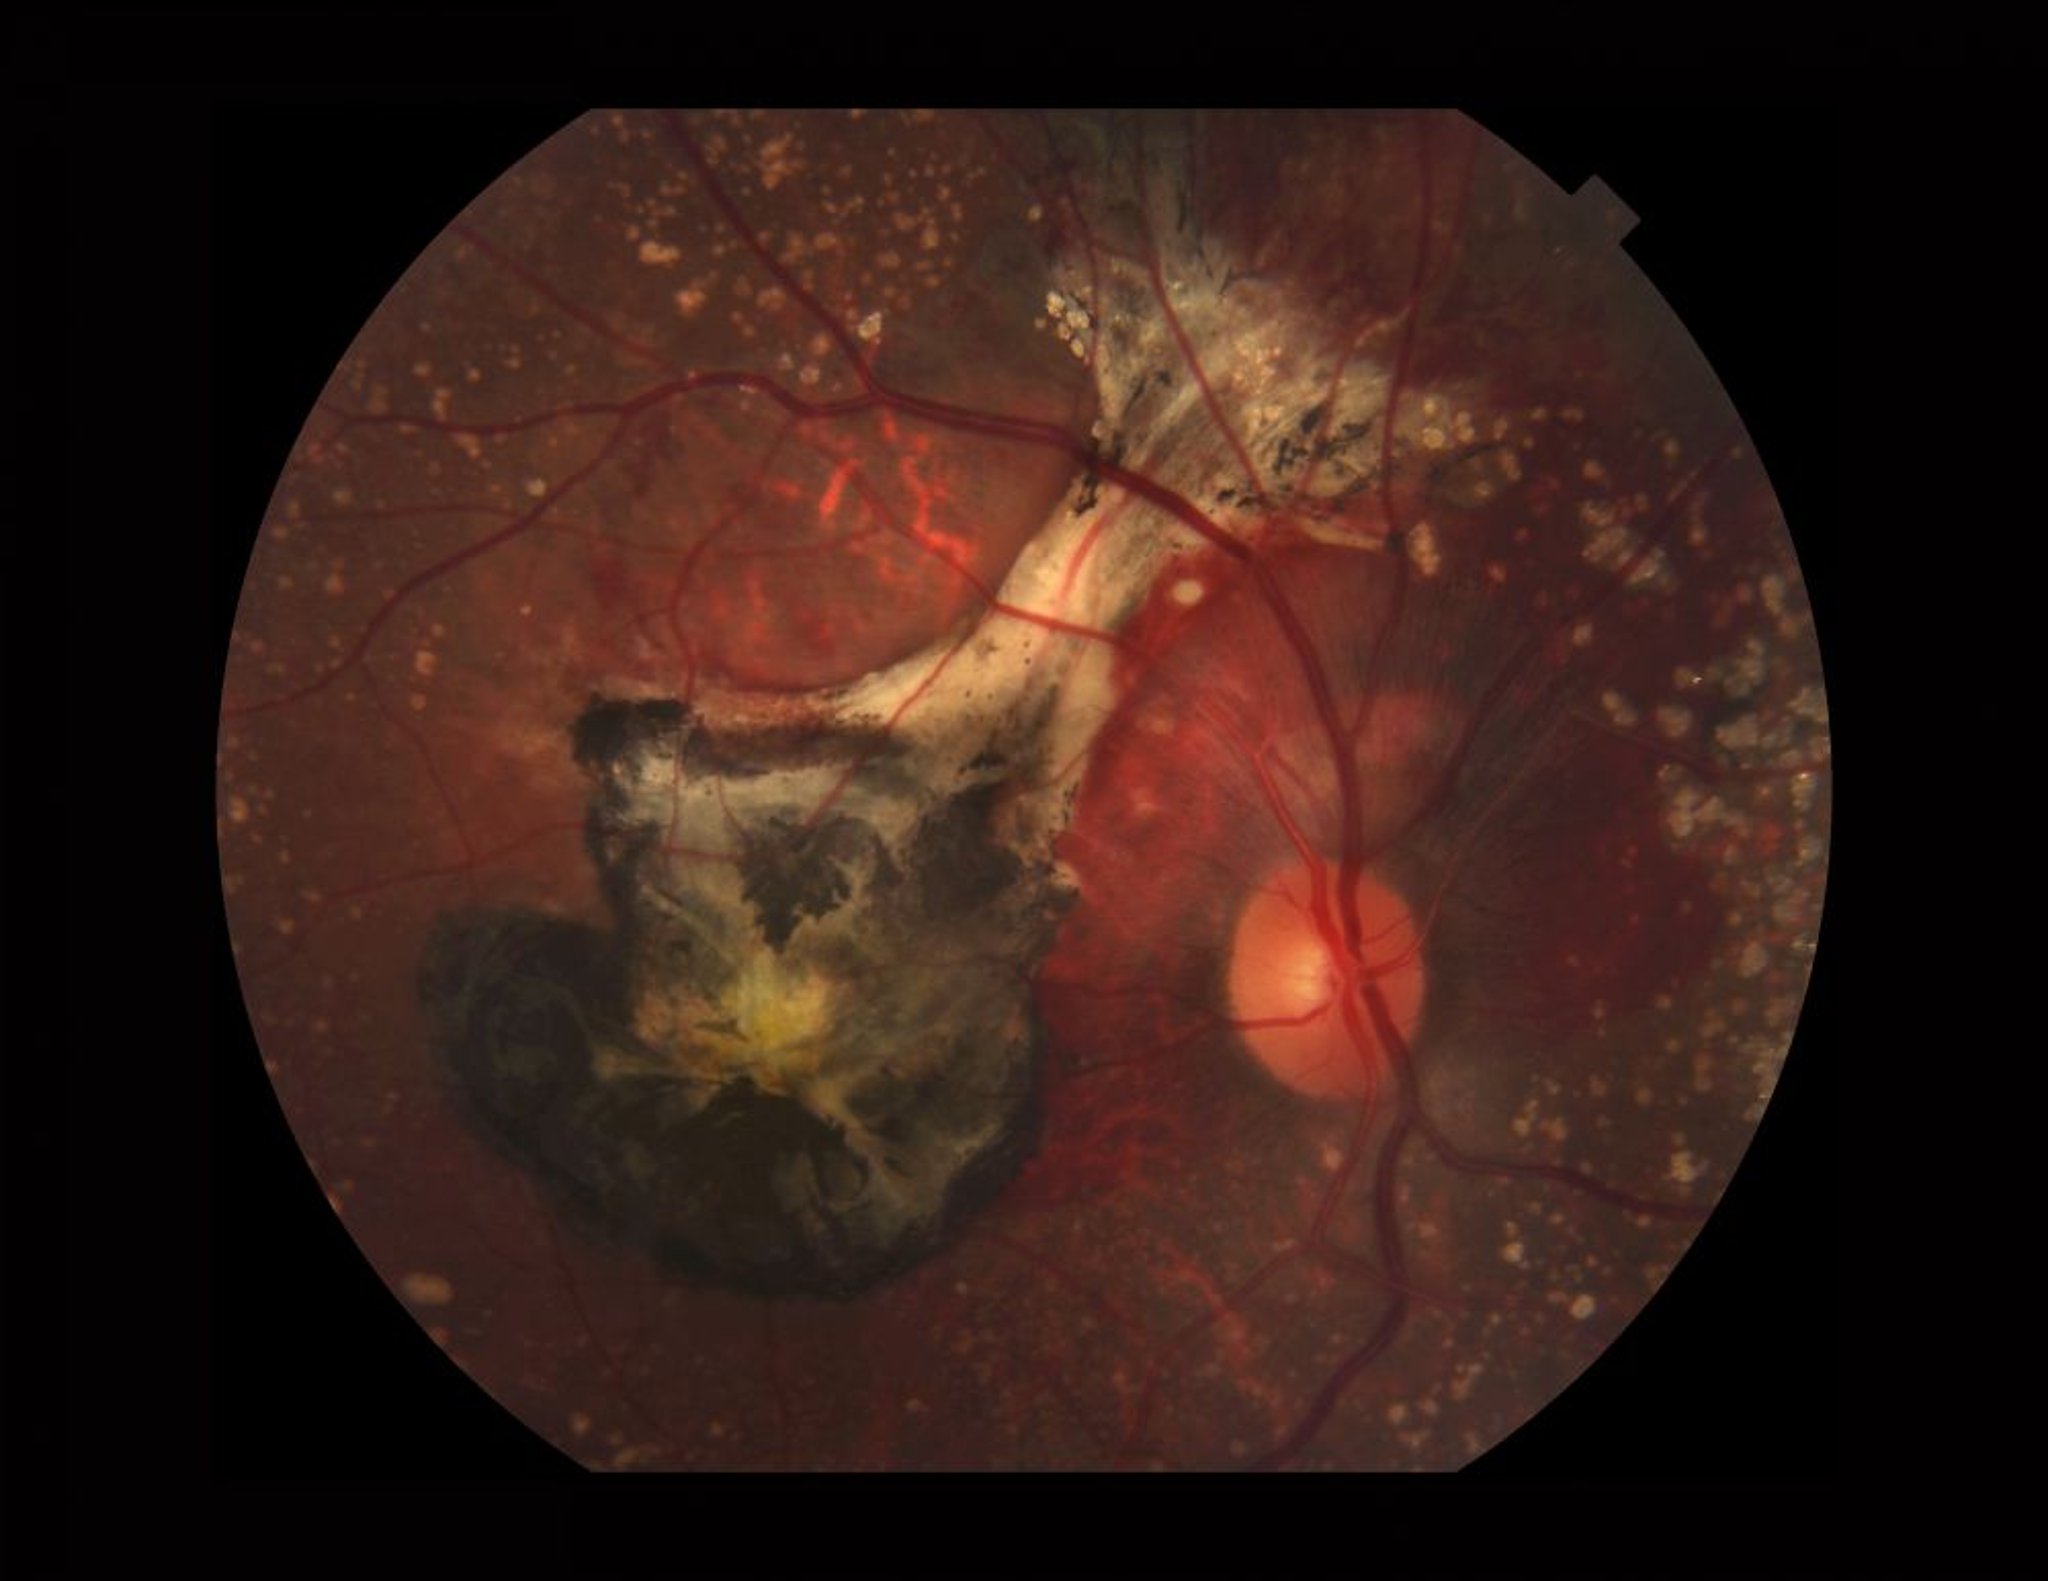

Thoái hóa điểm vàng liên quan đến tuổi (thể ướt)

Ảnh chụp võng mạc bị AMD thể ướt. Hình ảnh này cho thấy drusen bị vôi hóa, chảy máu dưới võng mạc, màng tân mạch ở màng mạch (màu đen do máu cũ và xơ hóa) và sắc tố xanthophyll (màu vàng) ở hoàng điểm.

PAUL WHITTEN/THƯ VIỆN HÌNH ẢNH KHOA HỌC